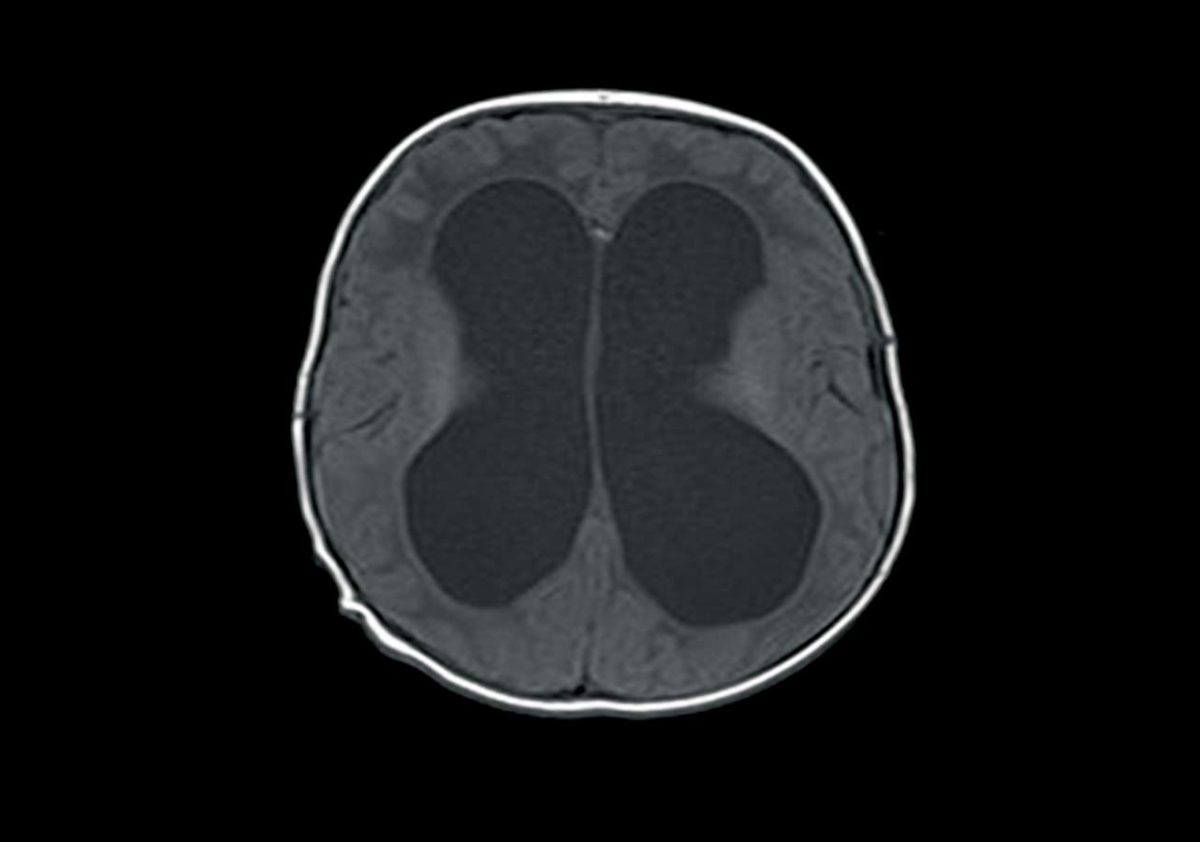

from radiologykey.com

Imaging of Cerebrospinal Fluid Shunts, Drains, and Diversion Techniques